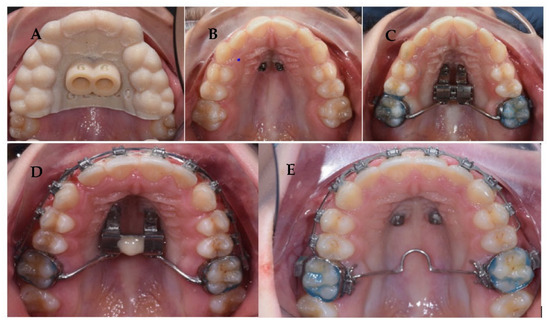

4. Case Report

4.3. Treatment Strategy

4.4. Treatment Progress